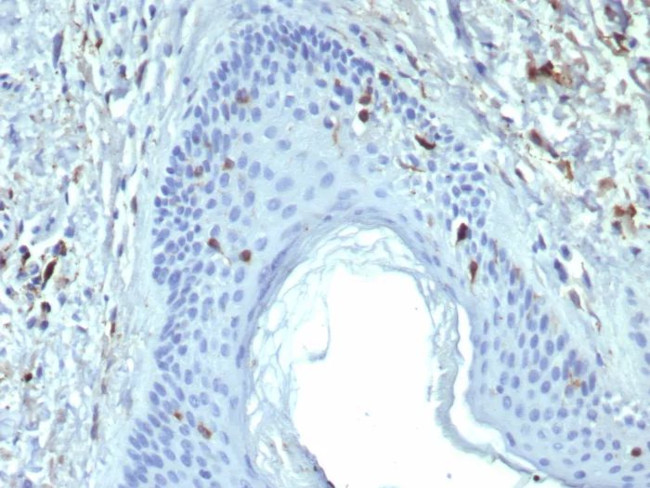

Langerin/CD207 (Marker of Langerhans Cells) Antibody in Immunohistochemistry (Paraffin) (IHC (P))

Langerin/CD207 (Marker of Langerhans Cells) Antibody (50489-MSM8-P1ABX) in IHC (P)

Formalin-fixed, paraffin-embedded human skin stained with Langerin Mouse Monoclonal Antibody (LGRN/7428). HIER: Tris/EDTA, pH9.0, 45 min. 2°C: HRP-polymer, 30 min. DAB, 5 min. {{ $ctrl.currentElement.advancedVerification.fullName }} 验证信息 View more

Positive Control:Human skin.

Cellular Location: Cell Surface. Cytoplasm.

Langerin (CD207) is a type II membrane-associated C-type lectin known to be expressed exclusively by Langerhans cells. Lamgerin recognizes mannose residues via its single carbohydrate recognition domain (CRD). Langerin is localized not only on the cell surface, but also intracellularly in close association with Birbeck granules. Transfection of Langerin cDNA into fibroblasts creates a compact network of membrane structures with typical features of Birbeck granules (BG). Langerin is thus a potent inducer of membrane superimposition and zippering leading to BG formation.